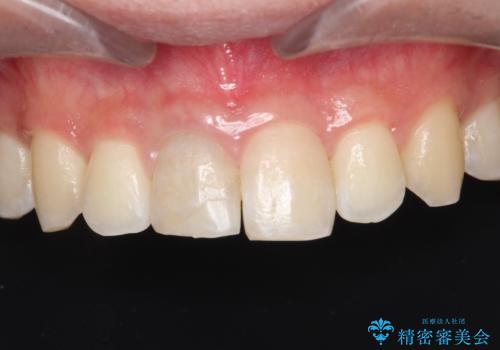

【ホワイトニング】右上前歯の歯茎の辺りが暗いのが気になる。

- 右上1番の色が暗いのを主訴に来院されました。

失活歯(神経の治療をしている歯)の場合、薬剤を歯の表面に塗布するホワイトニングでは白くなりません。歯の中に薬剤を入れて薬剤の反応を待つ必要があります。

治療手順としましては、マイクロスコープ(歯科用顕微鏡)を使用し、元々入っていた詰め物のCR(プラスチック)を除去します。その後、歯の中に薬剤を入れ、蓋をします。2週間後に来院して頂き、白くなっているかを確認します。ご本人がご満足頂く白さになるまで、これを3~4回繰り返します。今回は1回で患者様がご満足されたので治療を終了しています。